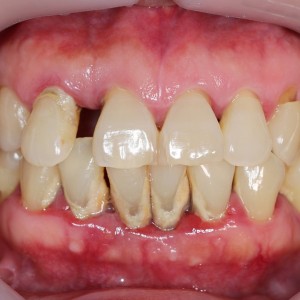

A new classification of periodontal diseases aimed to identify periodontal disease based on a multidimensional staging and grading system has been recently proposed. However, up to date, its prognostic predictive capability has not been investigated. The aim of this study was to assess if parameters included in the new classification were predictive of tooth loss after a long-term follow-up (>10 years) in patients with periodontitis.

Patients presented with periodontitis at the University of Michigan between January 1966 and January 2004 were screened and categorized according to the new classification of periodontitis. Number/Reasons of teeth loss in patients who underwent at least one session/year of maintenance during the entire follow-up period were extracted and used to analyze the prognostic capabilities of variables (staging, grading, and Extent) included in the new classification.

A total number of 292 patients with a mean follow-up of 289.7 ± 79.6 months were included. 31 (10.6%) patients were classified as Stage 1, 85 (29.1%) as Stage 2, 146 (50%) as Stage 3, and 30 (10.3%) as Stage 4. For grading, 34 (11.7%) were classified as Grade A, 193 (66.1%) as Grade B, and 65 (22.2%) as Grade C. Results of multilevel Cox regression analyses revealed a statistically significant association between stage (HR:3.73 between Stage 4 and Stage 1) and grade (HR: 4.83 between Grade C and Grade A) at baseline and periodontal related tooth loss, whereas no differences were detected for the extent of periodontitis.

This study provides the initial evidence regarding the predictive ability of the new classification of periodontitis. Patients in either Stage 4 or Grade C showed a significantly higher periodontal-related tooth loss.